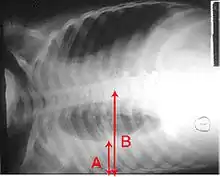

Рентгенографія часто використовується у діагностиці.[19] Пацієнтам із хворобою середньої важкості її проводять лише тоді, коли можливе ускладнення або ж тоді, коли діагноз непевний.[19][46] Якщо особа важко хвора і підлягає госпіталізації, то рентгенографія обов'язкова.[46] Результати не завжди збігаються із важкістю хвороби, і також за ними не можна впевнено розрізнити бактеріальну інфекцію від вірусної.[19]

За результатами рентгенограми можна класифікувати дольову пневмонію, бронхопневмонію (відому також як лобулярна пневмонія) та інтерстиціальну пневмонію.[49] Бактеріальна, позалікарняна, пневмонія класично показує ущільнення легень однієї сегментарної долі легень, що у свою чергу відоме як дольова пневмонія.[29] Проте, результати можуть різнитися, й інші зразки можуть показати інші типи пневмонії.[29] Аспіраційна пневмонія може бути у вигляді двостороннього затемнення в першу чергу в основі легень та з правого боку.[29] Рентгенограми вірусної пневмонії можуть виглядати як норма, занадто розширені легені, наявні осередкові області з обох боків або ж показувати типове для бактеріальної пневмонії дольове ущільнення.[29] Радіологічні показники можуть і не відобразитись на перших стадіях хвороби, особливо, якщо присутнє зневоднення; чи, коли їх важко інтерпретувати у пацієнтів з ожирінням або у тих, хто має захворювання легенів в анамнезі.[20] Сканування КТ може надати додаткову інформацію у невизначених випадках.[29]